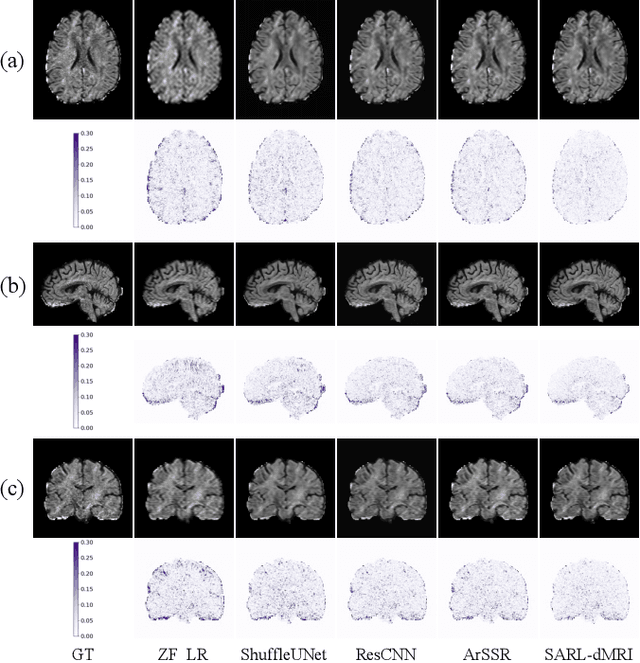

Abstract:Diffusion magnetic resonance imaging (dMRI) often suffers from low spatial and angular resolution due to inherent limitations in imaging hardware and system noise, adversely affecting the accurate estimation of microstructural parameters with fine anatomical details. Deep learning-based super-resolution techniques have shown promise in enhancing dMRI resolution without increasing acquisition time. However, most existing methods are confined to either spatial or angular super-resolution, limiting their effectiveness in capturing detailed microstructural features. Furthermore, traditional pixel-wise loss functions struggle to recover intricate image details essential for high-resolution reconstruction. To address these challenges, we propose SARL-dMRI, a novel Spatial-Angular Representation Learning framework for high-fidelity, continuous super-resolution in dMRI. SARL-dMRI explores implicit neural representations and spherical harmonics to model continuous spatial and angular representations, simultaneously enhancing both spatial and angular resolution while improving microstructural parameter estimation accuracy. To further preserve image fidelity, a data-fidelity module and wavelet-based frequency loss are introduced, ensuring the super-resolved images remain consistent with the original input and retain fine details. Extensive experiments demonstrate that, compared to five other state-of-the-art methods, our method significantly enhances dMRI data resolution, improves the accuracy of microstructural parameter estimation, and provides better generalization capabilities. It maintains stable performance even under a 45$\times$ downsampling factor.